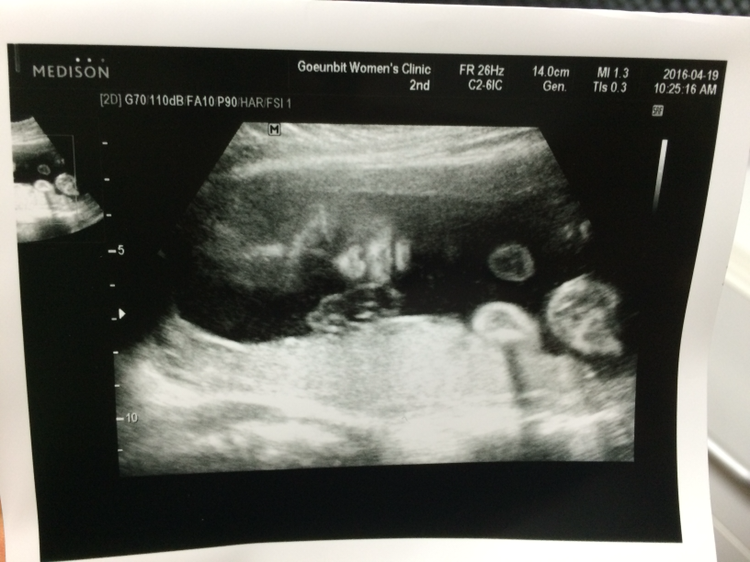

손에 조금만 피가 나도 대일밴드를 붙여댔고 샴푸 하나를 써도 바디로션 하나를 써도 몸에 좋은 걸 쓰게 되었다. 내 몸을 위해서가 아니었다. 혹시나 잘 못된 제품 사용으로 내 몸에 이상한 바이러스가 침투되거나 나쁜 유해성분들이 쓰며들어 혹 아이가 잘못될까 봐였다. 그래서 무조건 유기농, 천연, 인증마크가 있는 제품을 사용했다. 또 임신을 하니 안 그래도 심한 변비는 더 심해져 화장실을 가지 못하는 날이 많았지만 (임산부가 먹는 변비약이 있는데도) 그럼에도 불구하고 난 변비약은 먹지 않았다. 혹 아이에게 해가 될까 봐서였다. 무조건 식이요법을 했다. 그냥 나의 모든 삶은 뭐 하나를 해도 모두 뱃속에 있는 아이에게 맞추었다. 그런데 그게 끝이 아니었다. 임신을 하면서 자궁근종에 갑상선 호르몬 상승, 임신 당뇨, 거기에 (길가다가 갑자기 쓰러질 정도의) 심한 빈혈까지 생겼었다. 그래서 갑상선 호르몬 조절을 위해 한 달에 한 번씩 6개월까지 꼬박꼬박 병원에 가서 피를 뽑아야 했고, 자궁 검사를 위해 산부인과도 일주일에 한 번씩 가야 했다. 거기에 임신 당뇨에 먹는 것도 신경 써야 했고 그렇게 나는 아이를 지키기 위해 평소에 가지 않던 병원을 그렇게 싫어하던 병원을 한 달에 몇 번씩은 가야 했다. 팔, 엉덩이 할 거 없이 주삿바늘도 몇 번씩은 꽂아야 했고 말이다. 내 아이를 위해서... 나는 그래야만 했다.